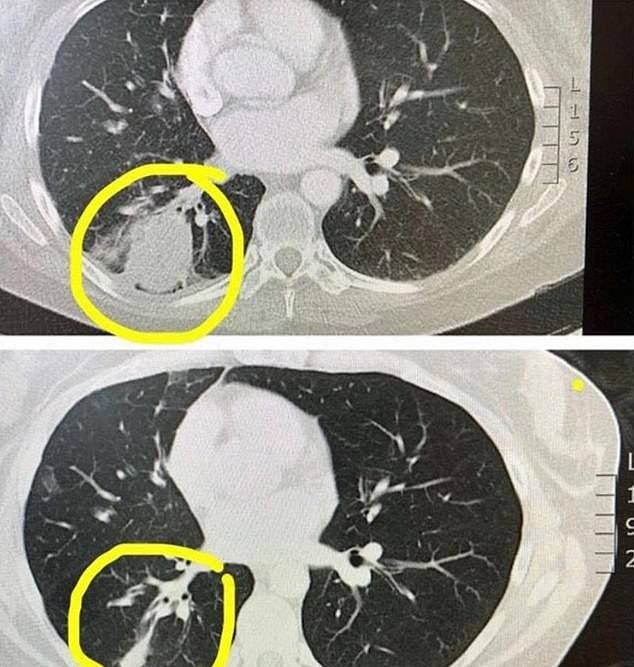

Comenzó a escupir sangre, lo que la llevó a visitar un hospital donde solo se le diagnosticó bronquitis. Con el tiempo su condición comenzó a empeorar rápidamente, por lo que que se le tomaron radiografías para revisar sus pulmones, ahí fue cuando se descubrió que estaba pasando.

Había una masa en sus pulmones y se temía que fuera cáncer. La posible enfermedad derrumbó el mundo de Kate, pero ella se negó a mostrarlo en su rostro, debía hacerlo por su pequeña hija Annabelle de apenas 3 años, debía ser fuerte por ella.

Después de revisar las radiografías y los otros posibles síntomas se confirmó que era cáncer de pulmón, una espantosa sorpresa para Kate que nunca había fumado en su vida, y para no estar sola en estos momentos fue a la consulta con sus padres que viajaron desde el Reino Unido para apoyarla.

En solo 12 semanas la terapia experimental de Kate ha tenido excelentes avances, el tumor en su pulmón se ha reducido un 75% y ella se niega a perder la pelea, lo hará por su hija que tanto adora y porque el futuro aún tiene muchas cosas para ella.

Hasta ahora los resultados han sido muy favorecedores y esperamos que tenga una pronta recuperación